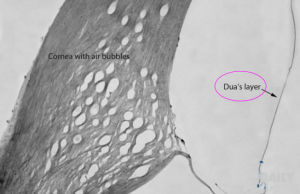

為了證明杜瓦層的存在,研究人員利用捐獻的眼球模擬角膜移植手術。在這些實驗中,科學家把微小的空氣氣泡注入角膜,把其中的各個結構層分離開來。通過電子顯微鏡,科學家發現了杜瓦層的存在。結構特點

杜瓦層位於角膜組織深處,在角膜基質層和後彈力層之間。它雖然只有1微米厚,但其韌性卻非常好,能夠承受1.5到2個大氣壓的壓力。發現意義